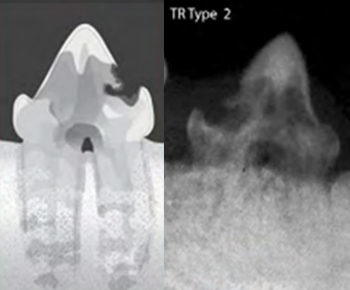

치아흡수병변 TYPE 및 예시

TYPE 2

치아흡수병변의 모습과 치아엑스레이 영상(Type2)